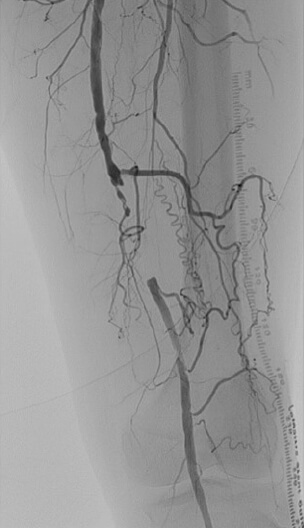

これらの血流が低下すると、歩行時の足の痛みや、足にできた傷が治らないなどの症状が出現します。これが下肢閉塞性動脈硬化症です。カテーテルを用いた実際の下肢動脈造影の映像がこのようになります(D)。

右腸骨動脈領域の閉塞 D

右腸骨動脈領域の閉塞

左浅大腿動脈の閉塞